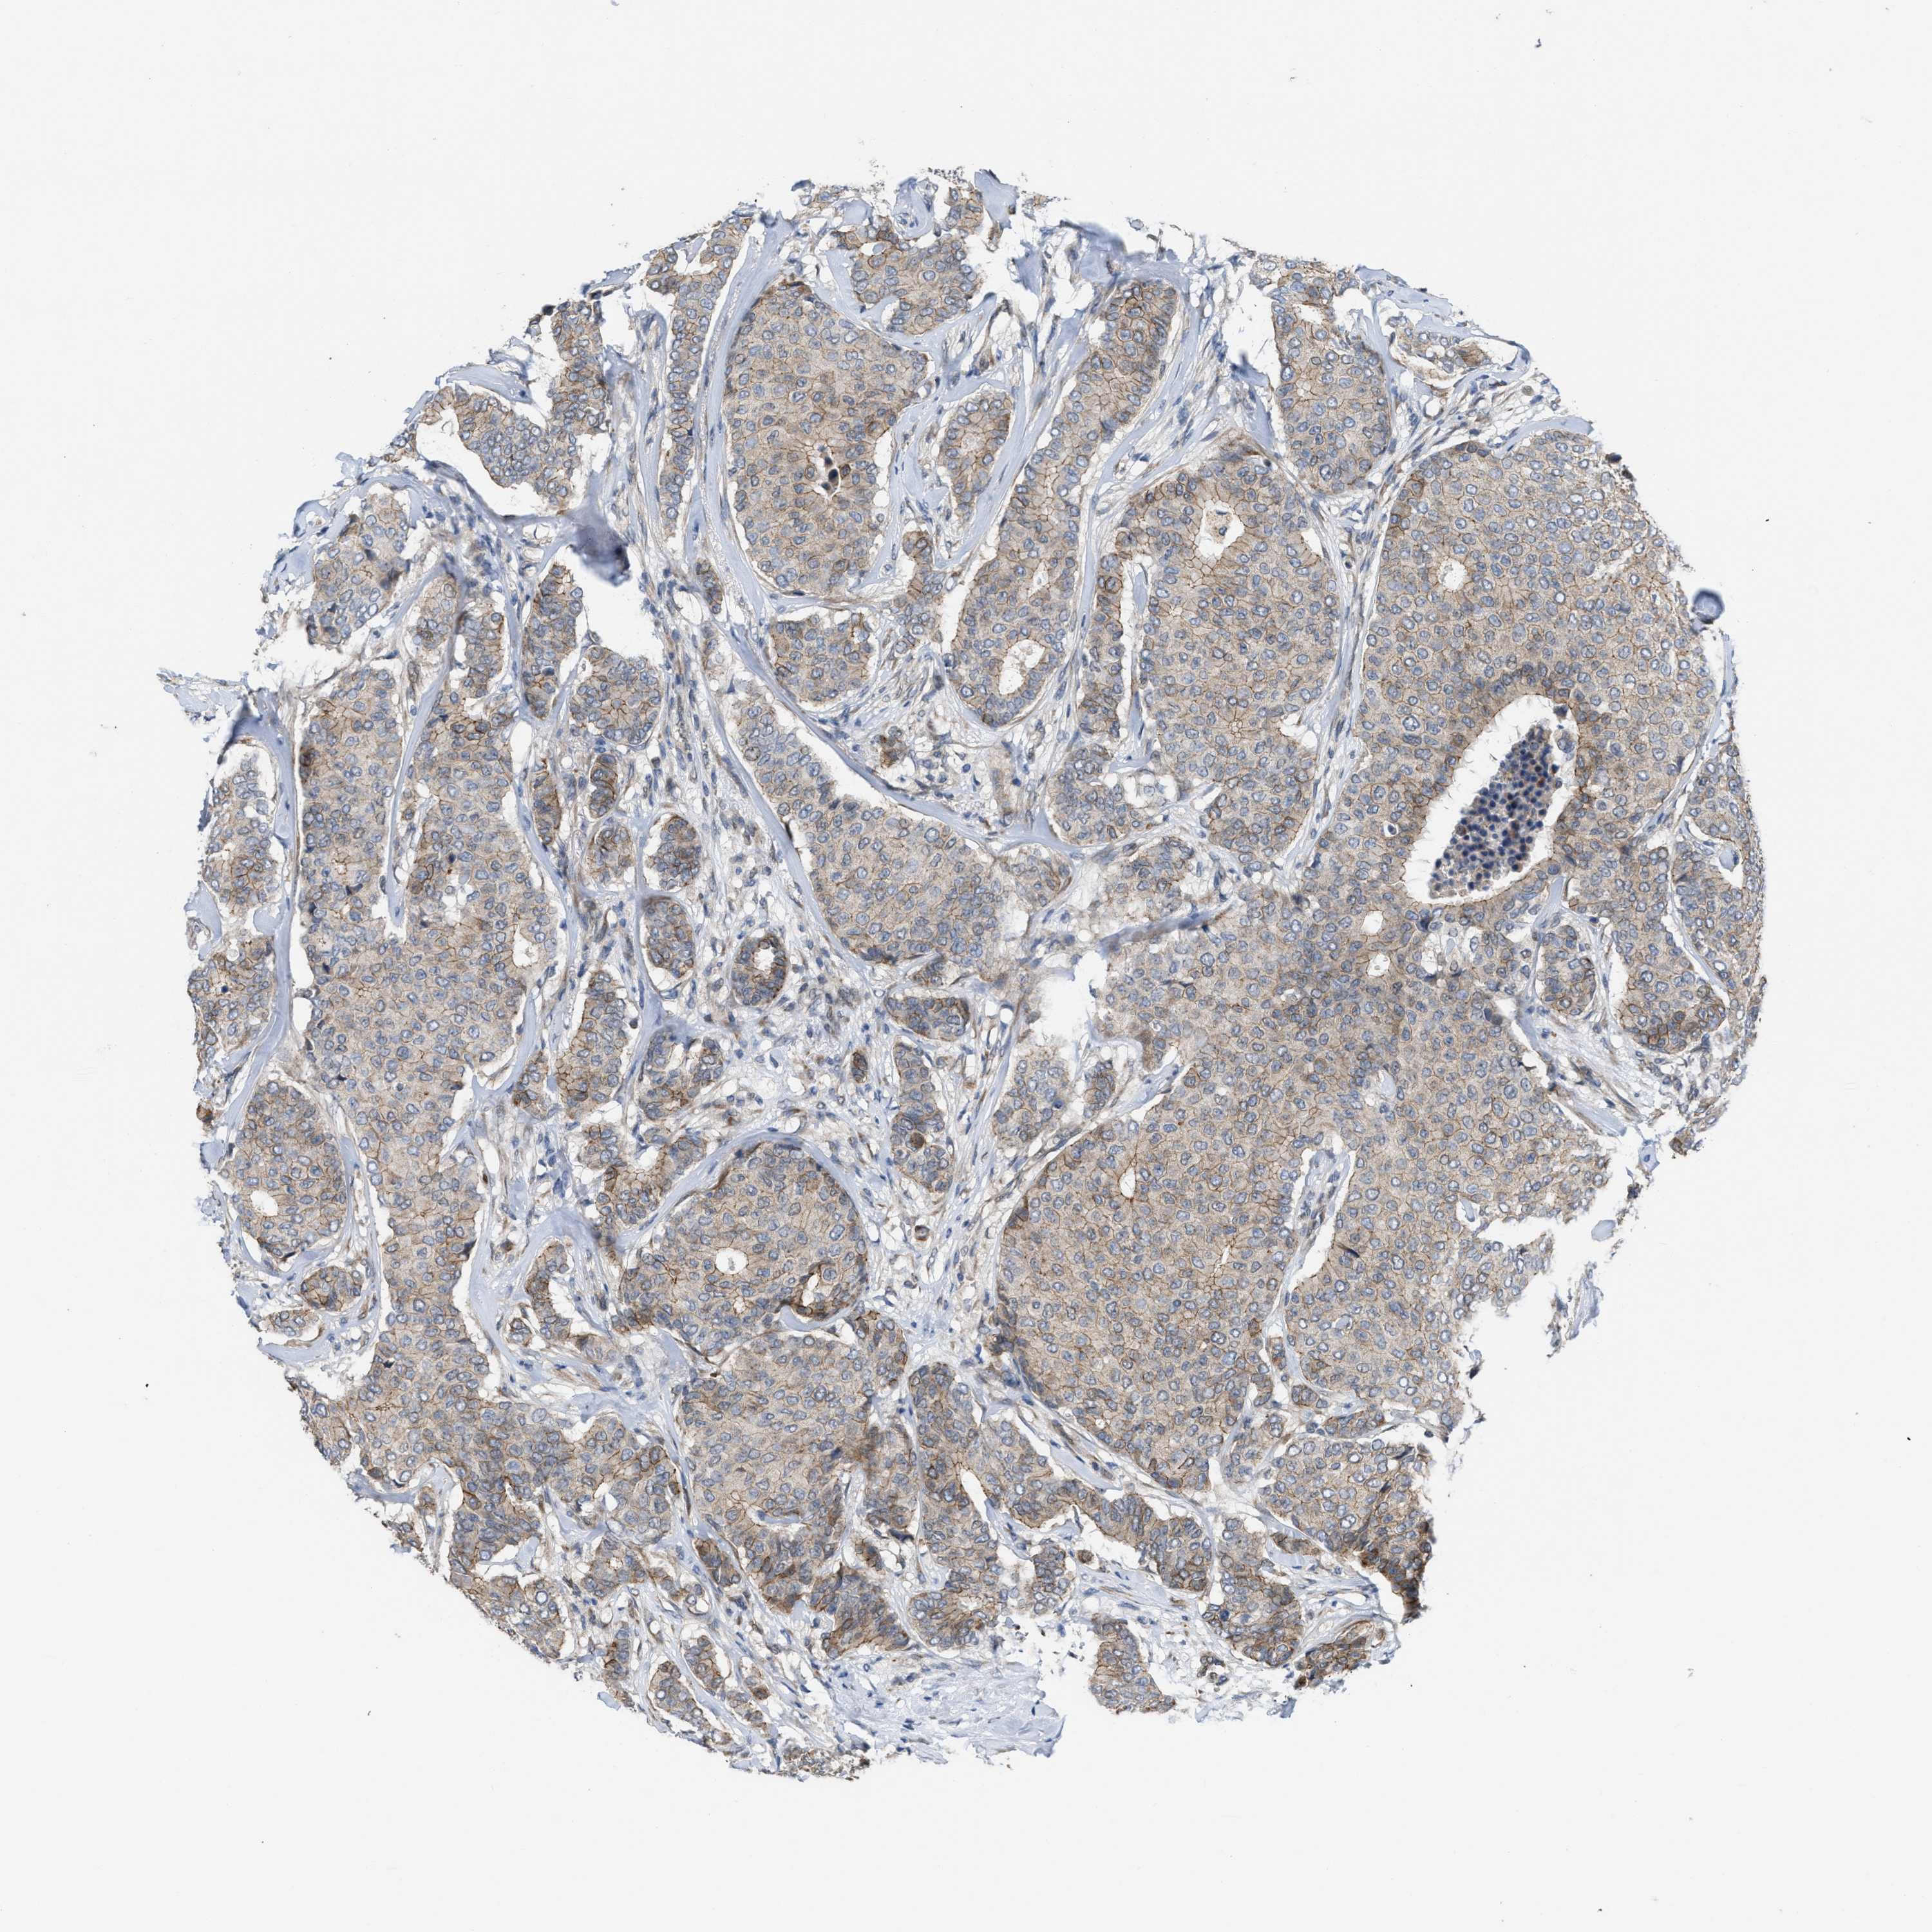

CANCER BREAST CANCER Show tissue menu

BRCA TCGA BRCA VALIDATION PROTEIN EXPRESSION